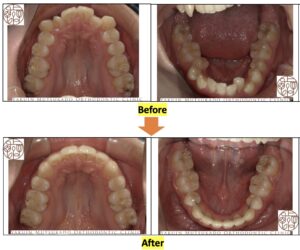

上下顎咬合面の治療前後の写真です↓↓

動的治療期間は約2年4ヶ月でした。定期的な通院や歯磨きを頑張っていただいたおかげで治療期間内に終わらせることができました。

性別:女性

年齢:10代

主訴:八重歯が気になる

診断名:叢生

動的矯正治療期間:2年4ヶ月

使用した装置:マルチブラケット装置(表側にメタルワイヤー)

抜歯部位:上下顎第一小臼歯

治療のリスク:歯肉の退縮、歯根吸収、歯髄充血、歯髄壊死など

治療費用総額(精密検査・診断、保定装置代含む、消費税込み):921,500円